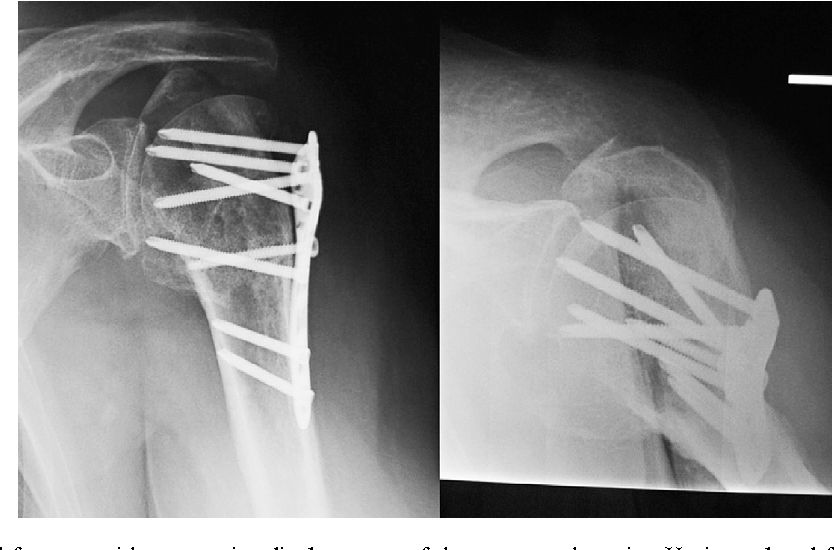

O.R.I.F. is an abbreviation for Open Reduction Internal Fixation. Open reduction internal fixation is a method of surgically repairing a fractured bone. Generally, this involves either the use of plates and screws or an intramedullary (IM) rod to stabilize the bone.

An open reduction and internal fixation (ORIF) is a type of surgery used to fix broken bones. This is a two-part surgery. First, the broken bone is reduced or put back into place. Next, an internal fixation device is placed on the bone; this can be screws, plates, rods, or pins used to hold the broken bone together.